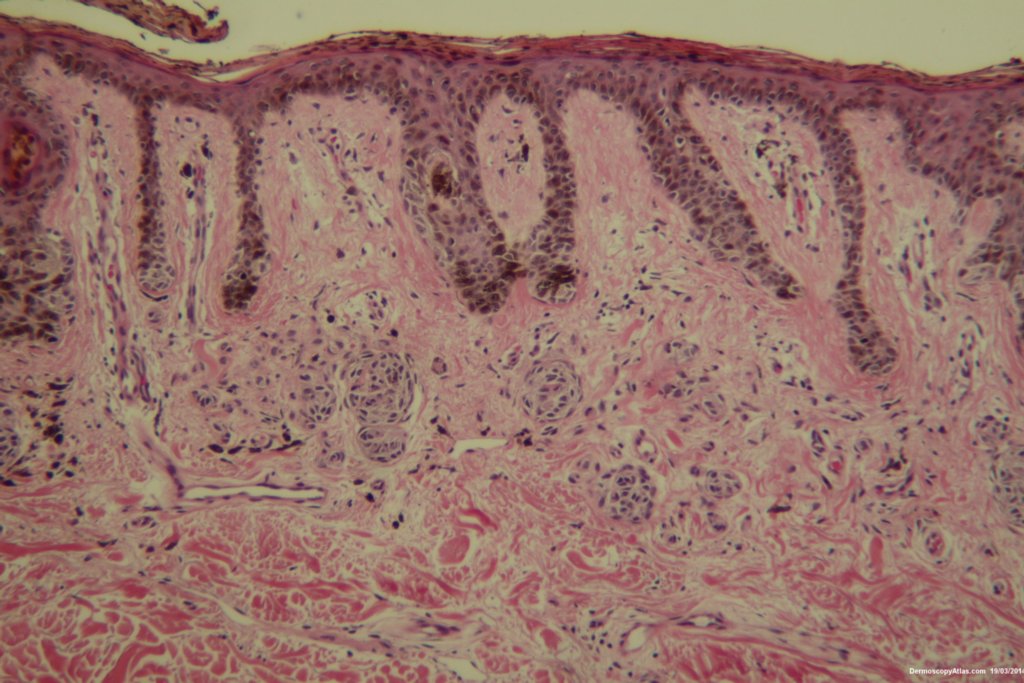

Diagnosis: Dysplastic Junctional Lentiginous Nevus

An elderly male asked about the pigmented lesion on his lower back. The dermatoscopy showed internal lines and dark clods with a central dark structureless area. Histology showed a dysplastic junctional lentiginous nevus.